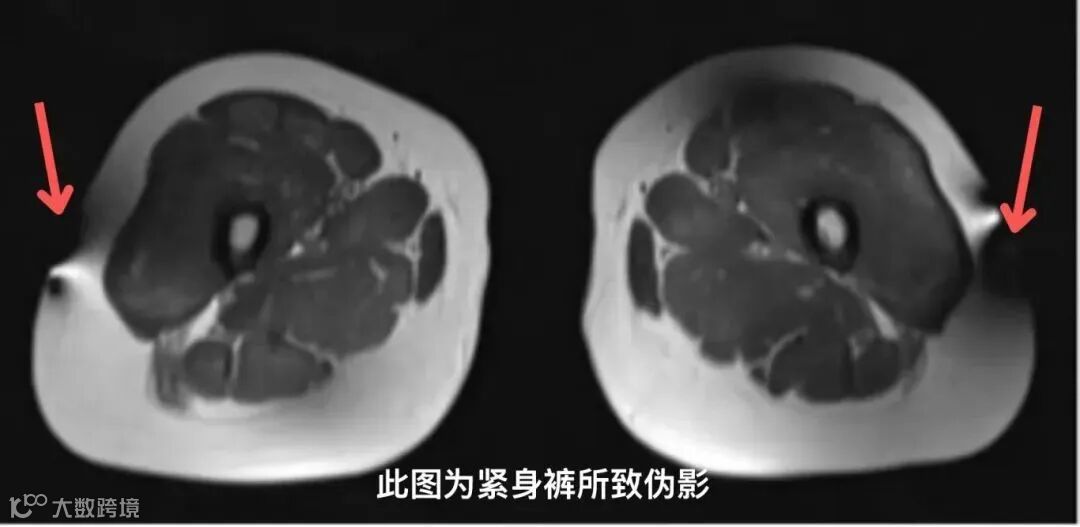

紧身瑜伽裤、磁疗内衣裤

很多人都知道做MRI检查不能带金属,但健身品牌会将金属纤维加入一些运动服装中,例如lululemon的瑜伽裤这类内嵌入银和铜纤维的纺织品,通过抗菌特性来控制气味,但如果穿这种含金属纤维的衣服做磁共振,检查过程中材料会升温,可能会导致接受检查的患者烧伤。

注意注意!穿lululemon瑜伽裤,请谨慎做磁共振检查!